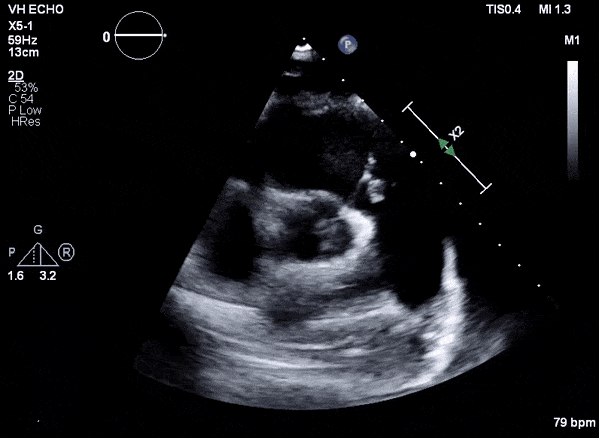

Role of Echocardiography

- Echo plays an important role in the diagnosis of infective endocarditis.

- Helps identify vegetations, new valvular lesions, abscess, and other complications of endocarditis.

- Transthoracic (TTE) should be performed in all cases of suspected infective endocarditis

- Transesophageal (TEE) should be performed if TTE images are inadequate or ongoing suspicion for infective endocarditis.

Case 2 (Pulmonic Valve IE)